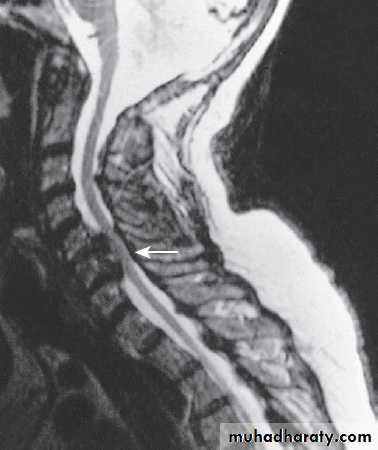

Cervical, thoracic and lumbar spine

Plain X-rays are useful in the investigation of trauma toVertebrae. MRI has transformed the investigation of these areas, since it can give information not only about the vertebrae and intervertebral discs, but also about their effects on the spinal cord and nerve roots.

Myelography is an invasive technique involving injection of contrast into the lumbar theca. While the outline of the nerve roots and spinal cord provides information about abnormal structure, the accuracy and wide availability of MRI have reduced the need for this.

Myelography may still be used for technical reasons or where MRI is unavailable, contraindicated, or precluded by the patient’s claustrophobia.